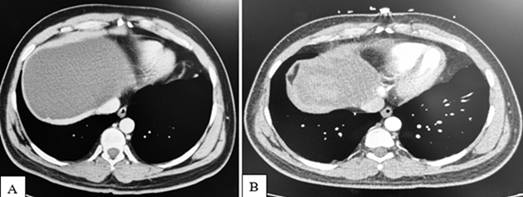

Simple hepatic cysts are considered to be a benign disease found in approximately 1-5% of the general population.1 Patients with hepatic cysts infrequently experience complications such as infection, torsion, or spontaneous ruptura.1 Very few cases have documented external compression of nearby structures by hepatic cysts, leading to inferior vena cava (IVC) or right atrial compression.1-3 Compression of the IVC (Figure 1A) can lead to venous stasis and subsequent thrombus formation (e.g. deep vein thrombosis, pulmonary embolism).

Contrast-enhanced CT imaging can be used to confirm the presence of a large simple cyst exerting mass effect on the IVC (Figure 1A). One potential treatment option involves percutaneous drainage of the cyst for decompression (Figure 1B).1 For more advanced cases, laparoscopy, mechanical thrombectomy, and anti-thrombolytic therapy may be warranted.1,2 Additional testing may be indicated to rule out conditions such as malignancy, echinococcus infection, Entamoeba histolytica infection, or autosomal dominant polycystic kidney disease.

Figure 1 Computed Tomography (CT) imaging with contrast of the abdomen of a 38 year old male demonstrating a large hepatic cyst before (A) and after

(B) percutaneous drainage. Prior to intervention, the hepatic cyst caused extrinsic compression of the inferior vena cava (IVC) (A), contributing to the development of bilateral pulmonary emboli. He had no risk prior risk factors for thrombosis. In Figure 1B, after placement of an IVC filter and deflation of the cyst via percutaneous drainage, the hepatic cyst is significantly decreased in size with resolution of IVC compression.